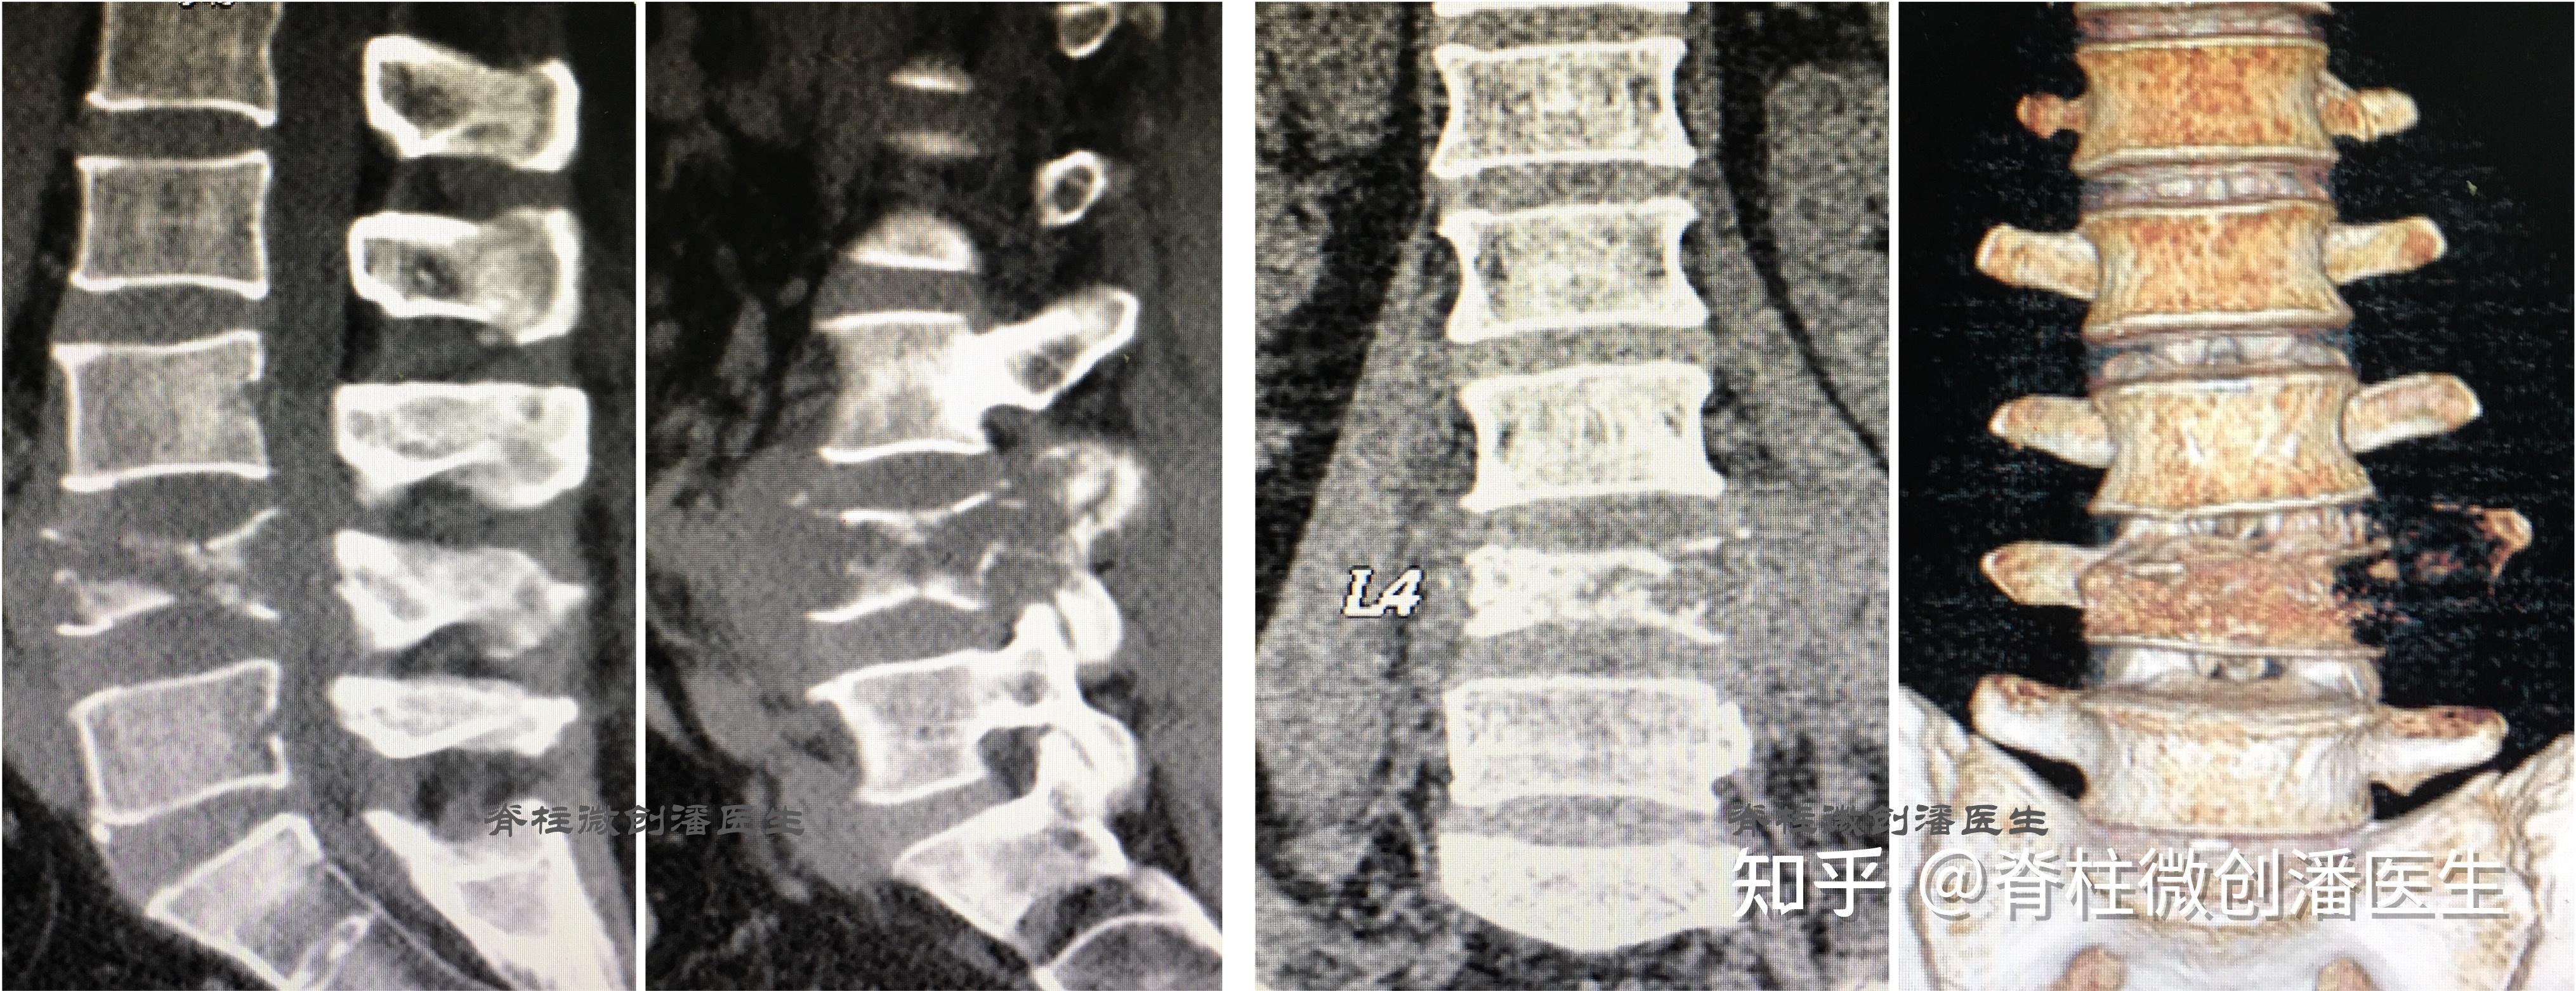

脊柱肿瘤的微创手术,2天出院!

最常见的脊柱肿瘤——脊柱转移瘤